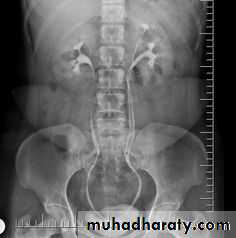

High density renal stonesStage horn calculus KUB filmsradio opaque stones

Normal IVU series